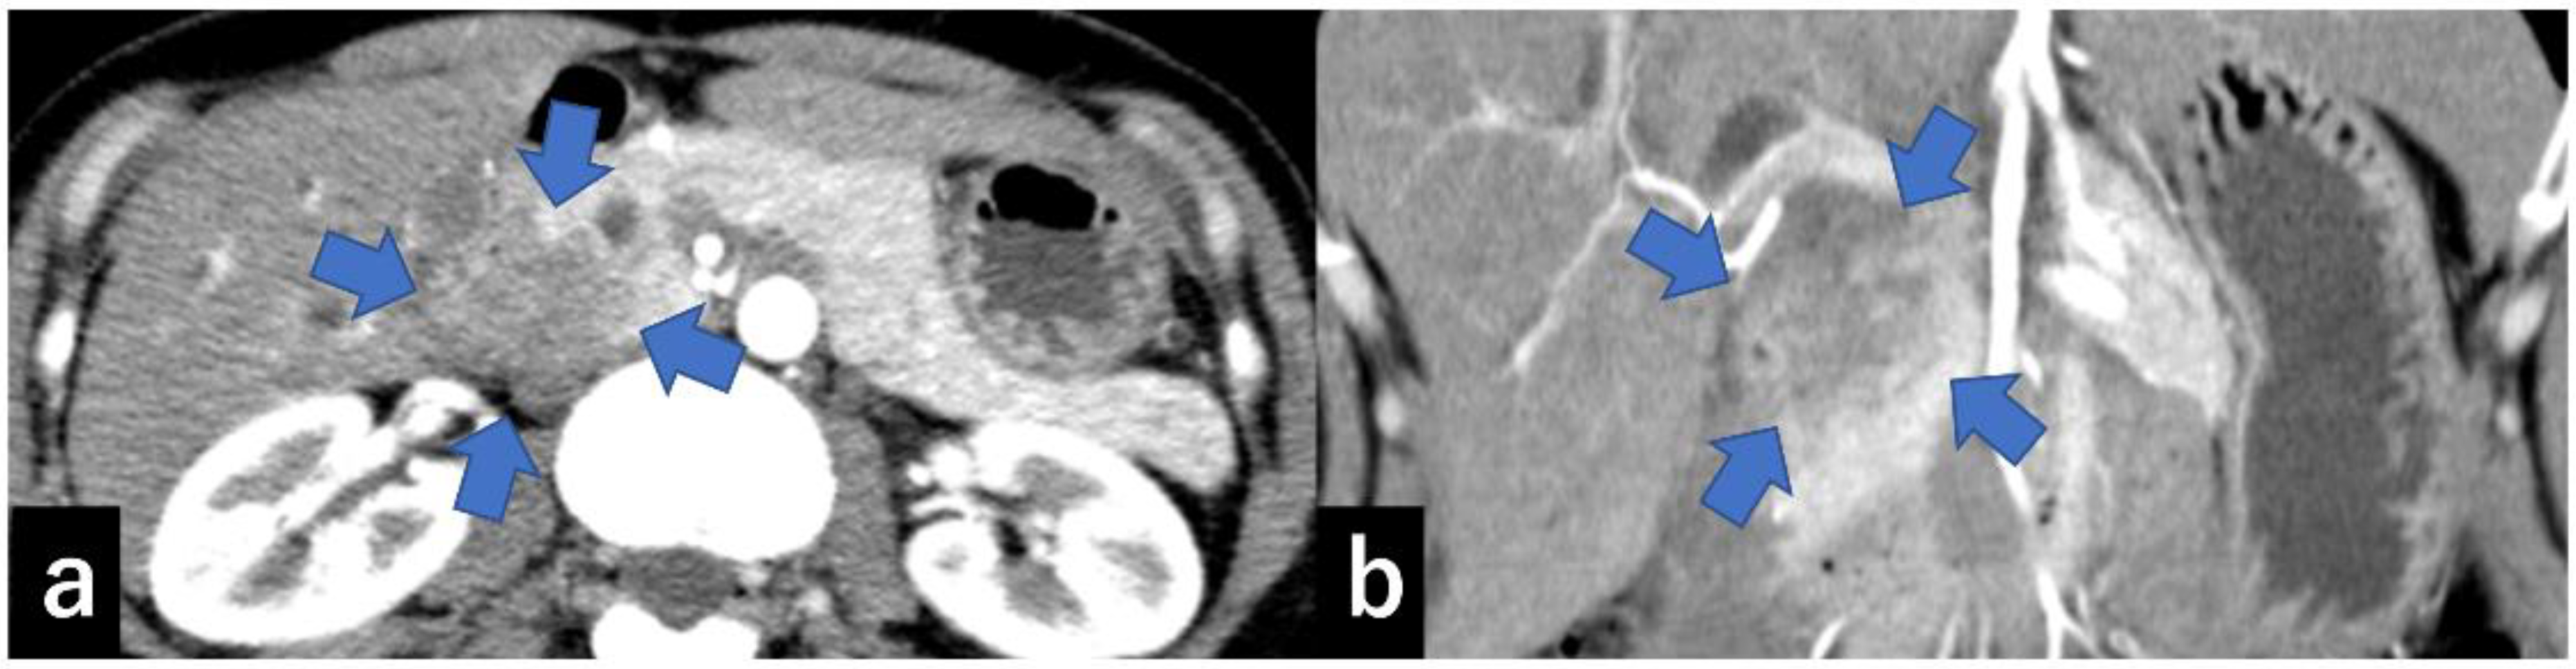

3.3. Imaging Findings